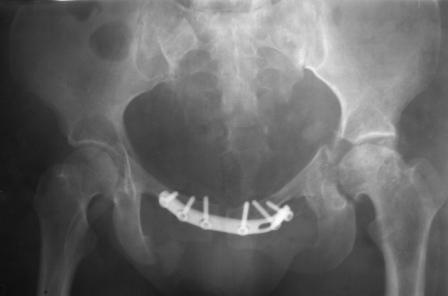

Направлена к нам для устранения патологической установки стопы и эндопротезирования левого тазобедренного сустава, также имеется миграция шурупов пластины, фиксирующей лонное сочленение.

Клинически: ходит на костылях с нагрузкой на правую ногу. Левая стопа в эквинусе. Осевая нагрузка на левую н\конечность болезненна в области левого тазобедренного сустава, при прикосновениях к подошвенной поверхности стопы у пациентки чувство зжения. В левом коленном суставе полный обьем движений, в левом тазобедренном резко ограничено отведение и ротация, укорочение левой н\конечности на 2,5 см. При полипроекционной и функциональной Р-графии выявлена нестабильность левого КПС и лонного сочленения, консолидированный в порочном положении поперечный оскольчатый перелом левой вертлужной впадины с центральным смещением головки бедра. Нами выполнена коррекция деформации левой стопы. Планируется выполнить введение 2 канюлированных илиосакральных винтов слева, реостеосинтез лонного сочленения реконструктивной пластиной, после заживления ран - тотальное эндопротезирование левого тазобедренного сустава.

Вопросы: 1. достаточно-ли предпологаемой фиксации тазового кольца, может быть добавить аппарат внешней циксации;

2. сроки установки эндопротеза;

3. методика установки вертлужного компонента.